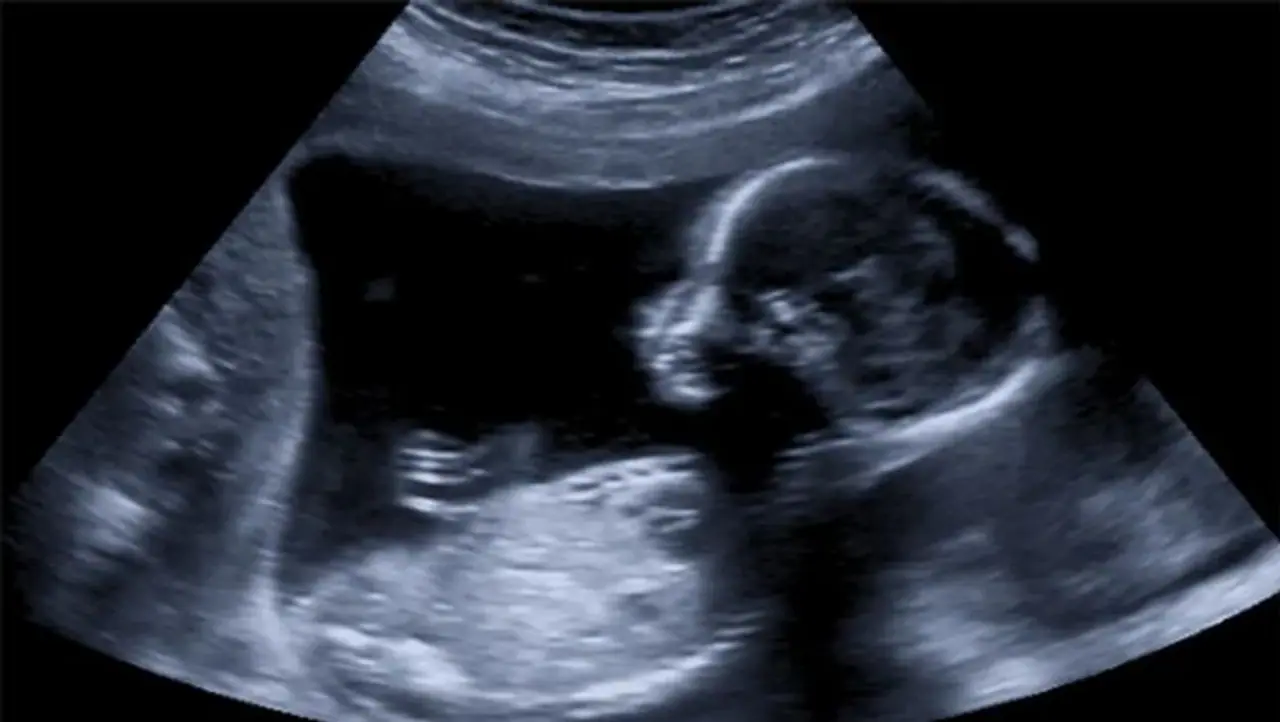

அல்ஜீரியா நாட்டைச் சேர்ந்த 75 வயது மூதாட்டி ஒருவர் கடந்த 35 ஆண்டுகளாக வயிற்றில் குழந்தையை சுமந்து வந்த செய்தி உலகம் முழுவதும் பலரையும் ஆச்சரியத்தில் உறைய வைத்துள்ளது. அல்ஜீரியாவில் உள்ள ஸ்கிக்டாவை சேர்ந்த 73 வயதாகும் மூதாட்டிக்கு சமீபத்தில் வயிற்று வலி ஏற்பட்டிருக்கிறது. இதையடுத்து மருத்துவமனைக்கு சென்ற மூதாட்டிக்கு மருதுவர்கள் எக்ஸ் ரே எடுத்துள்ளனர். அப்போது ஒளிப்படத்தில் கண்ட காட்சியைக் கண்டு மருத்துவர்கள் ஆச்சர்யத்தில் உறைந்தனர். மூதாட்டிக்கு எடுக்கப்பட்ட எக்ஸ்ரேவில் அவரது வயிற்றில் குழந்தை இருப்பது கண்டுபிடிக்கப்பட்டது.

73 வயதாகும் மூதாட்டி எப்படி கருவுற்றிருக்க முடியும் என்று சோதனை செய்தபோது அதைவிட பெரும் அதிர்ச்சி காத்திருந்தது. மூதாட்டியின் கருவறையில் இந்த குழந்தை சுமார் 35 ஆண்டுகளுக்கு முன்னர் உருவாகியுள்ளது. சுமார் ஏழு மாதங்களுக்கு பின்னர் வளர்ச்சிதையடைந்த குழந்தை கல்லாக மாறியுள்ளது. சுமார் 2 கிலோ எடைகொண்ட இந்த கல் குழந்தையை மூதாட்டி சுமார் 35 ஆண்டுகளாக சுமந்து வந்துள்ளார். கருவுற்றிருந்த போதும் மாதவிடாய் சரியாக வந்தது எப்படி என்றும் மருத்துவர்களிடம் மூதாட்டியின் உறவினர்கள் விளக்கம் கேட்டுள்ளனர்.

பாதிக்கப்பட்ட அல்ஜீரியா மூதாட்டிக்கு சுமார் 35 ஆண்டுகளுக்கு முன்னர் இந்த கரு உருவாகியுள்ளது. அப்போது கருவானது அவரது அடி வயிற்றிற்குள் சென்று அங்கிருந்து வெளியேர முடியாமல் அங்கேயே வளர்ச்சி அடைந்துள்ளது. ஏழு மாதங்களுக்கு பின்னர் கரு வளர்ச்சி அடையாமல் இருந்துள்ளது. வளர்ச்சிதை அடைந்த அந்த கரு கல் குழந்தையாக மாறியுள்ளது. கரு முட்டைக்குள் குழந்தை தங்காமல் அடி வயிற்றிற்கு சென்றுவிட்டால் அவருக்கு மாதவிடாய் சரியாக இருந்துள்ளது. இந்த காலக் கட்டத்தில் அவரது உடல் எடை மட்டும் கூடியுள்ளது. ஆனால் அது வயது முதிர்வால் ஏற்படும் மாற்றம் என நினைத்து அப்பெண் கல் குழந்தையை சுமந்து வந்துள்ளார். ஏழு மாதத்திற்கு பின்னர் குழந்தை வளர்ச்சிதை அடைந்ததால் அதனை உடம்பில் உள்ள நோய் எதிர்ப்பு சக்தி வெளியே தள்ள முயற்சி செய்திருக்கும் அது கைகூடாமல் போனதால் குழந்தை கல்லாக மாறியுள்ளது. 2 கிலோ கல் குழந்தையை 35 வருடங்களாக சுமந்து வந்த மூதாட்டி வயிற்றில் இருந்து அறுவை சிகிச்சை மூலம் கல் குழந்தையை மருத்துவர்கள் அகற்றியுள்ளனர். இடைப்பட்ட காலங்களில் மூதாட்டிக்கு அதிர்ஷ்டவசமாக எந்த வித உடல் பாதிப்பும் ஏற்படவில்லை.